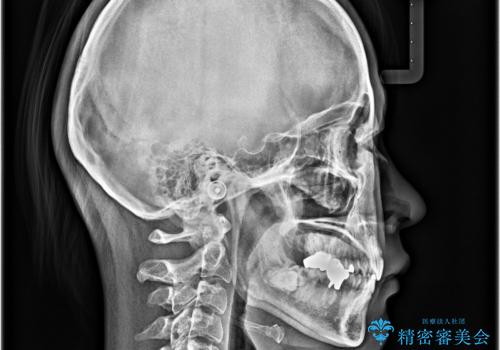

- 口元の突出感と奥歯のむし歯を気にして来院された患者様です。

奥歯の虫歯は事前に矯正治療用の仮歯に置き換えて矯正治療を行い、装置除去後にセラミッククラウンにて補綴治療を行うこととしました。

通常は上下左右の第一小臼歯4本を抜歯することになりますが、左側下顎の第二小臼歯は既に根管治療をされており、予後が良くないとのことでこの歯を抜歯し、ワイヤー装置にて矯正治療を行うこととしました。

第二小臼歯抜歯はイレギュラーな治療手段であり、治療期間が延びる傾向にありますが、予定よりも早い2年間で終えることができました。